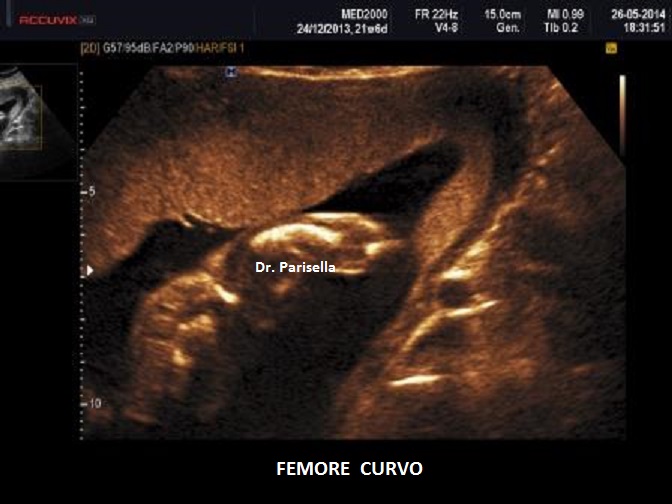

Quella che interessa dal punto di vista della diagnosi ecografica prenatale è l'Osteogenesi Imperfetta tipo II (OMIM 166210) caratterizzata da fragilità ossea con fratture multiple, micromelia severa dovuta alle fratture delle ossa lunghe, ipoplasia toracica severa a volte con fratture costali, ipomineralizzazione diffusa del cranio.  Ecograficamente si manifesta con ossa corte, ricurve e fratturate (le ossa fratturate si presentano angolate); ossa craniche scarsamente ossificate (tanto che la volta cranica può avere una ecogenicità simile a quella della linea mediana) con conseguente migliore evidenza e definizione delle strutture cerebrali e segno caratteristico la deformabilità della teca cranica.;  ipoplasia toracica con fratture costali; IUGR; movimenti fetali scarsi.